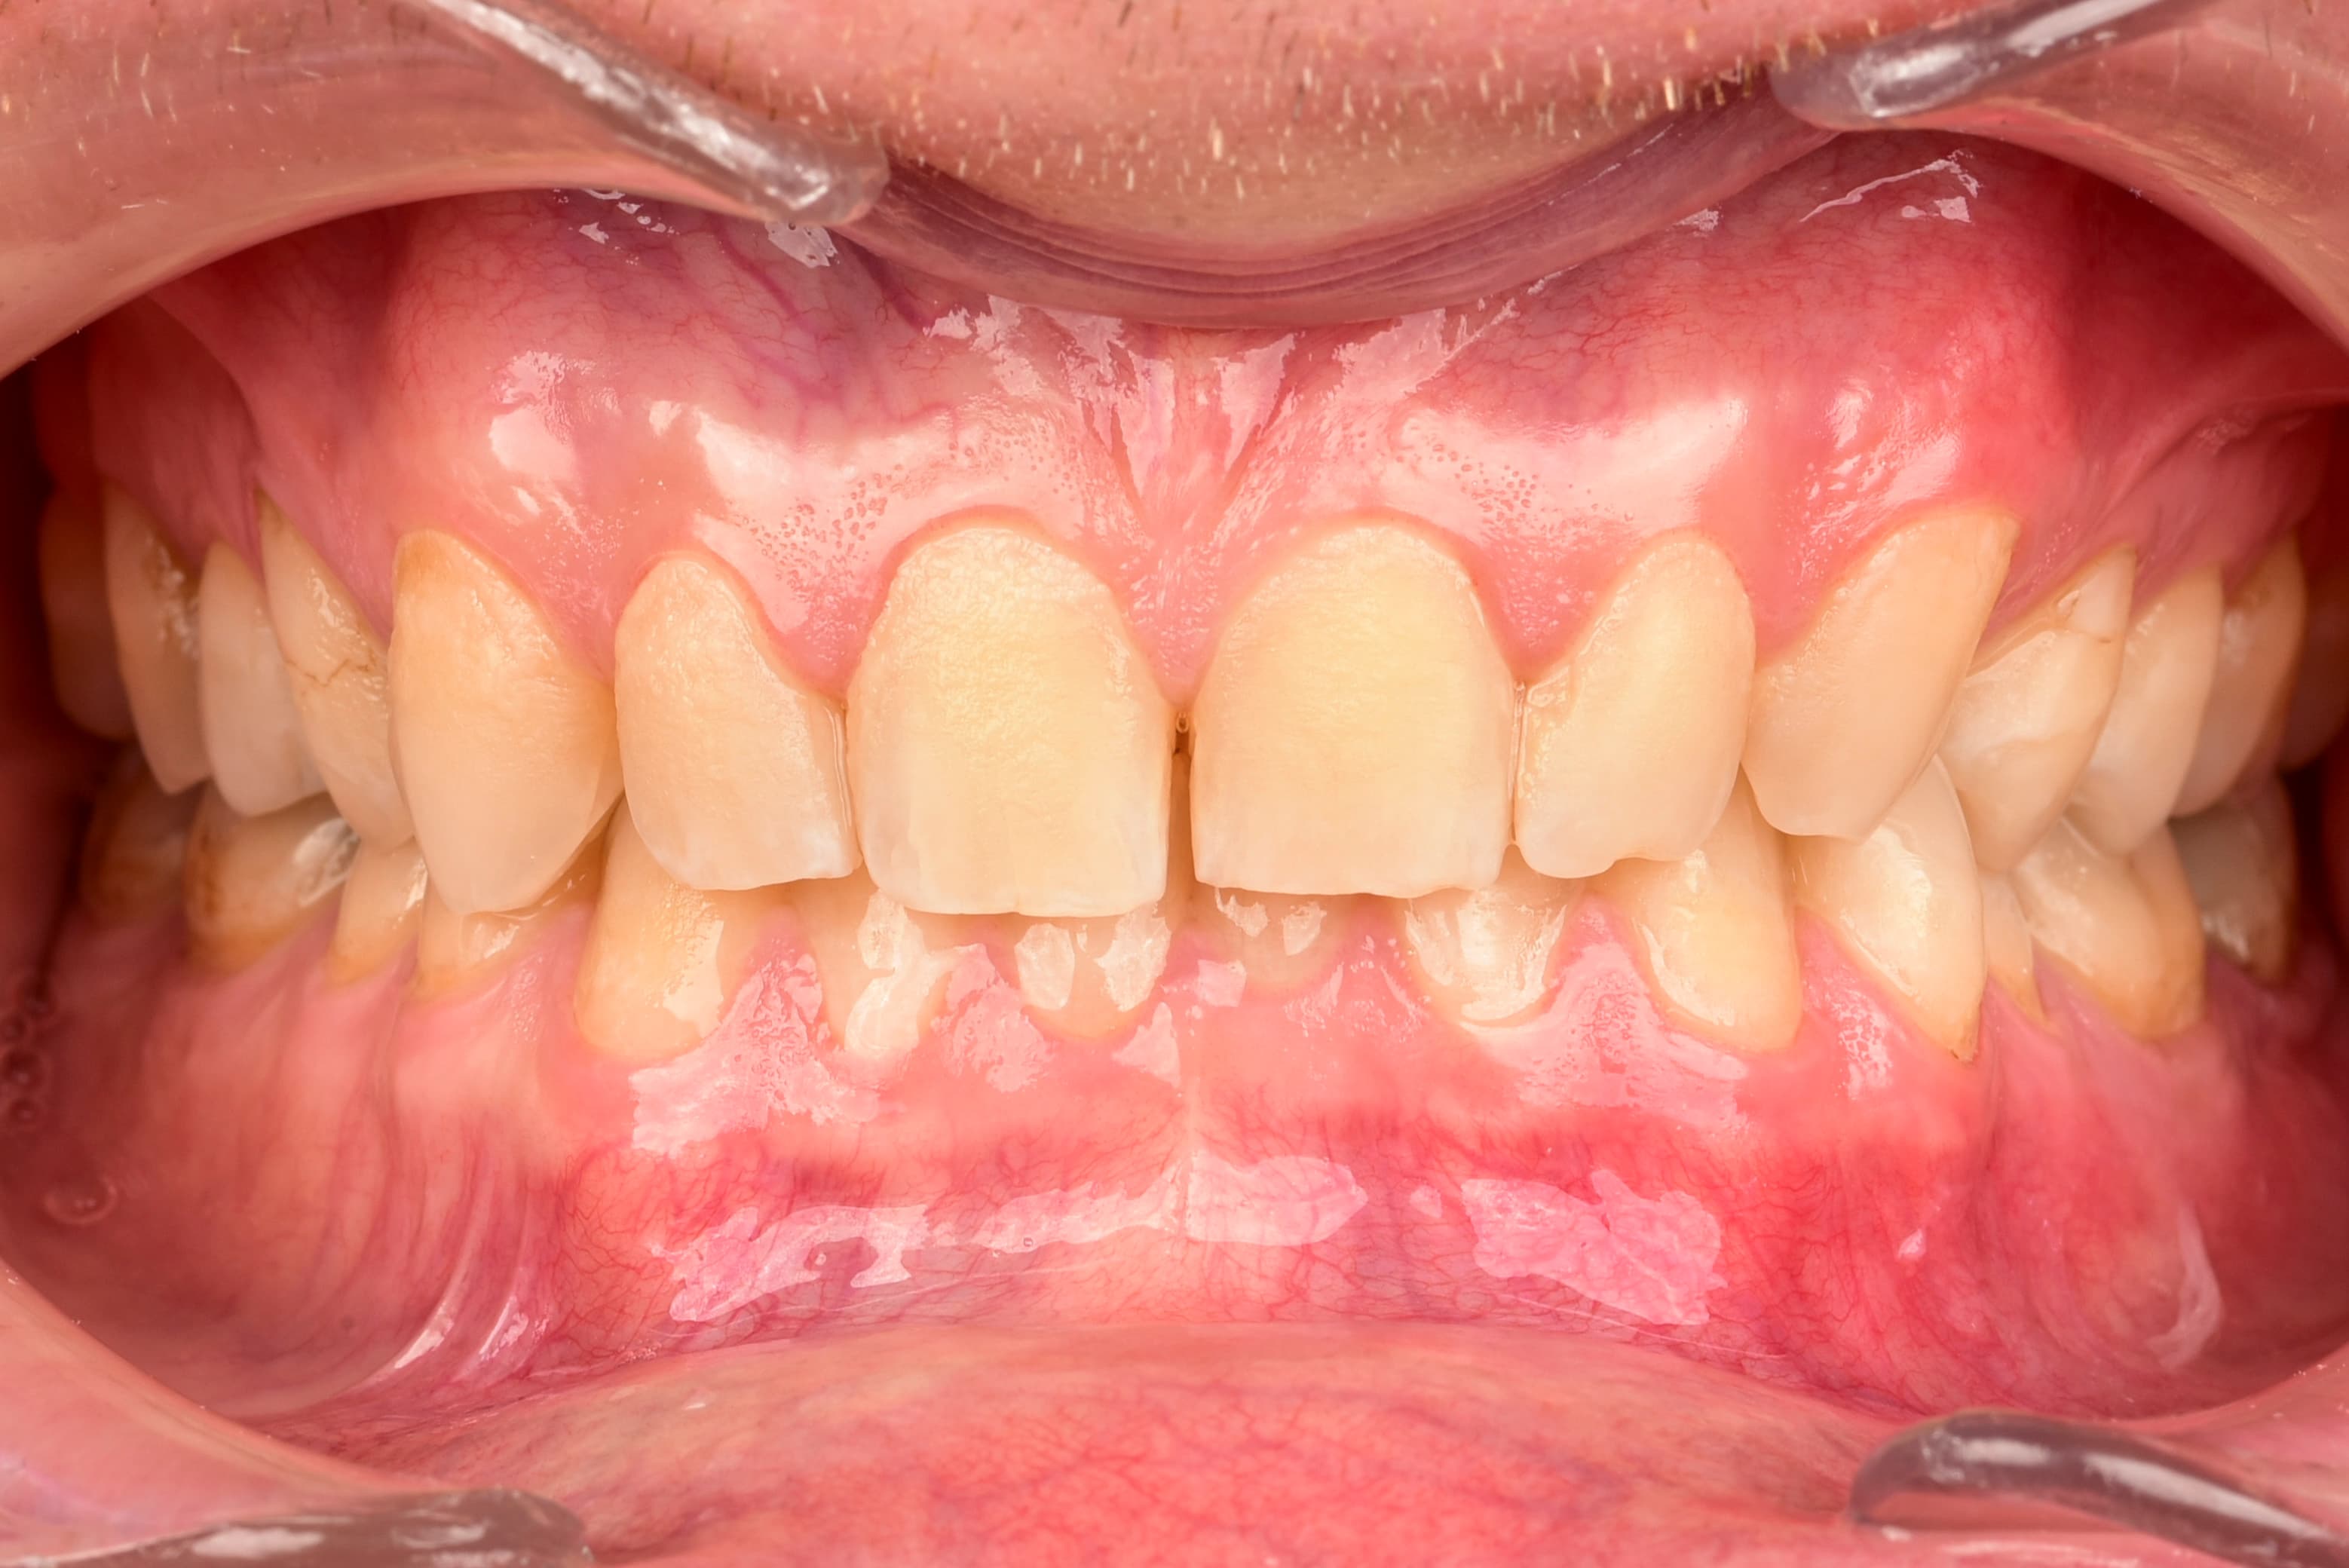

- My gums have become more pink and nicer.

- After the 6th day, my teeth really did become smoother and more shiny than I ever remember in my life. There was no such effect for the first 3–5 days.

Healthier gums – The disappearance of bleeding, swelling or redness of the gums is a sign that inflammation is decreasing and the oral microflora is returning to balance.

Healthier gum color – A light pink color of the gums is a sign of good blood supply and lack of inflammation.